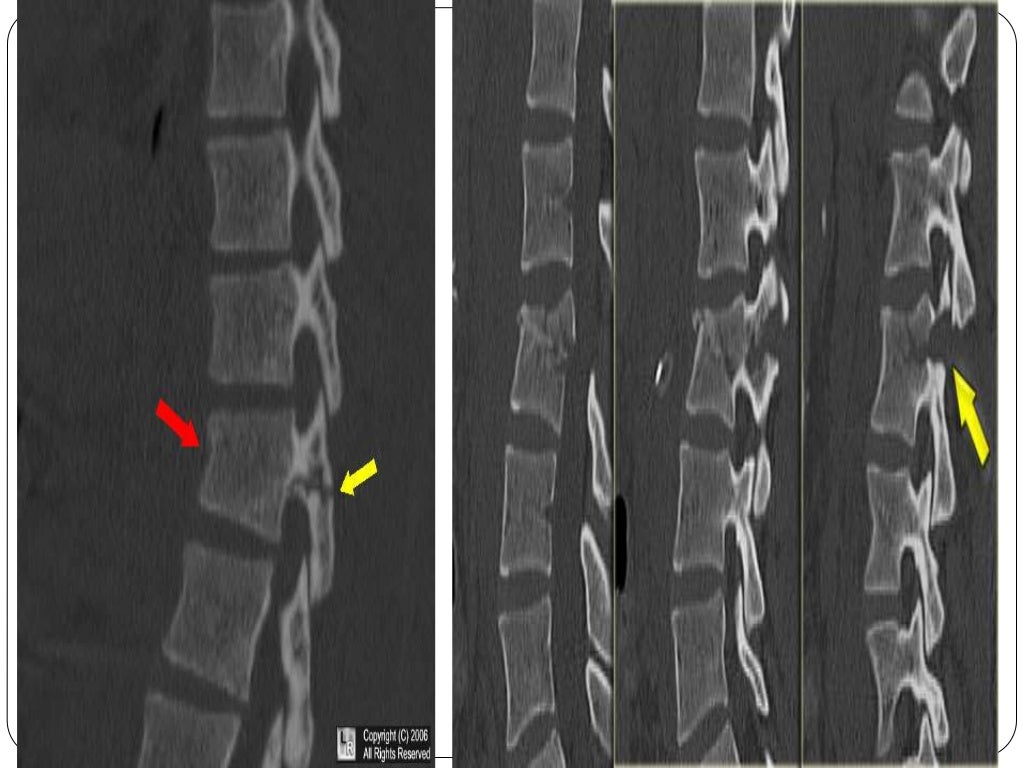

Fracture types Plaster Of Paris tecniques and Complications